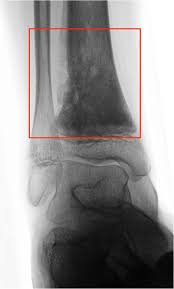

It is important that all these symptoms are identified at an early stage so, to. Or, the cause of a symptom may be a different medical condition that is not cancer. In some cases, doctors will notice a tumor around that particular area of the bone. People with a fracture next to or through a bone tumor usually describe sudden severe pain in a bone that had been sore for a few months. Osteosarcoma, the most common bone cancer, usually happens to people ages 10 to 30 and most often starts in the arms, legs, or pelvis. See foot cancer stock video clips. The bone may look ragged, or it may appear to have a hole in it. Grade 2 (g2) falls somewhere in between. What bone metastasis looks like. Foot or toe cancer (digital and soft tissue cancer), which can include squamous cell carcinoma, melanoma, osteosarcoma, mast cell tumor, and malignant soft tissue sarcoma is common in dogs. They can be primary (originating in the bone) or secondary (originating in another part of the body). Lumps, swellings, fractures, joint tenderness and pain are some common symptoms of bone cancer in ankle and foot. Learn enough about bone cancer to make decisions about your care.

Pain from bone tumors can originate from within the bone. Symptoms of a bone tumor may include: As you learn more about bone cancer, you may become more confident in making treatment decisions. The world health organization has identified 82 different benign and malignant foot lesions. Basal cell cancers may appear as pearly white bumps or patches that may ooze or crust and look like an open sore. Although rare, bone tumors can occur in the foot and ankle. Occasionally a mass or swelling in the area. Grade 1 (g1) means the cancer looks much like normal bone tissue. Sometimes, people with bone sarcoma do not have any of these changes. Each of these types of cancer has their own set of symptoms and treatment, but the main symptom in all of these is a swelling or ulcer on the foot or toe. Bone cancer can weaken the bone it's in, but most of the time the bones do not fracture (break). A benign bone tumor of the foot will manifest as a lump, with or without pain, whereas bone cancer is most often accompanied by pain at the location of the tumor. Whether primary or metastatic, cancer in the bones may present with symptoms such as increasing pain, swelling and/or a more sudden intense pain from a pathologic fracture —a fracture that occurs in a bone that has been weakened by the presence of tumor.

Lumps, swellings, fractures, joint tenderness and pain are some common symptoms of bone cancer in ankle and foot. Squamous cell carcinoma is the most common form of cancer on the skin of the feet. Early on, the pain may only occur at night, or when you are active. When a bone tumor grows, it presses on healthy bone tissue and can destroy it, which causes the following symptoms: The bone may look ragged, or it may appear to have a hole in it.